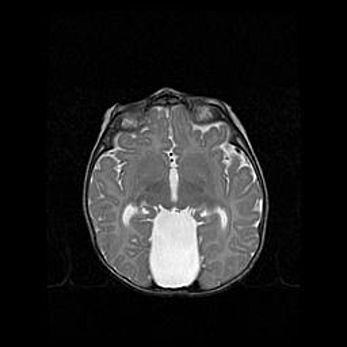

Церебральная ишемия II.

Возраст: 5 дней

Вес: 3400 г

Пол: женский

Окружность головы: 35 см

Срок гестации: 39 недель

Церебральная ишемия – это заболевание, характеризующееся недостаточностью (гипоксией) либо полным прекращением (аноксией) снабжения мозга кислородом по причине закупорки одного или нескольких сосудов. Это приводит к  что метаболическим расстройствам различной степени тяжести в тканях головного мозга, развитию коагуляционных некрозов и гибели нейронов.